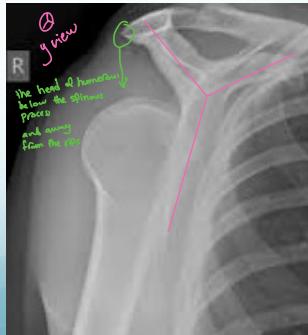

X-ray Findings:

- AP view:

- The humeral head is medially rotated → “Electric light bulb” sign

- The empty glenoid sign

- Posterior displacement

- Axillary & Scapular views are essential

- Rule-out fractures: neck, lesser tuberosity, glenoid

- CT Scan if still in doubt